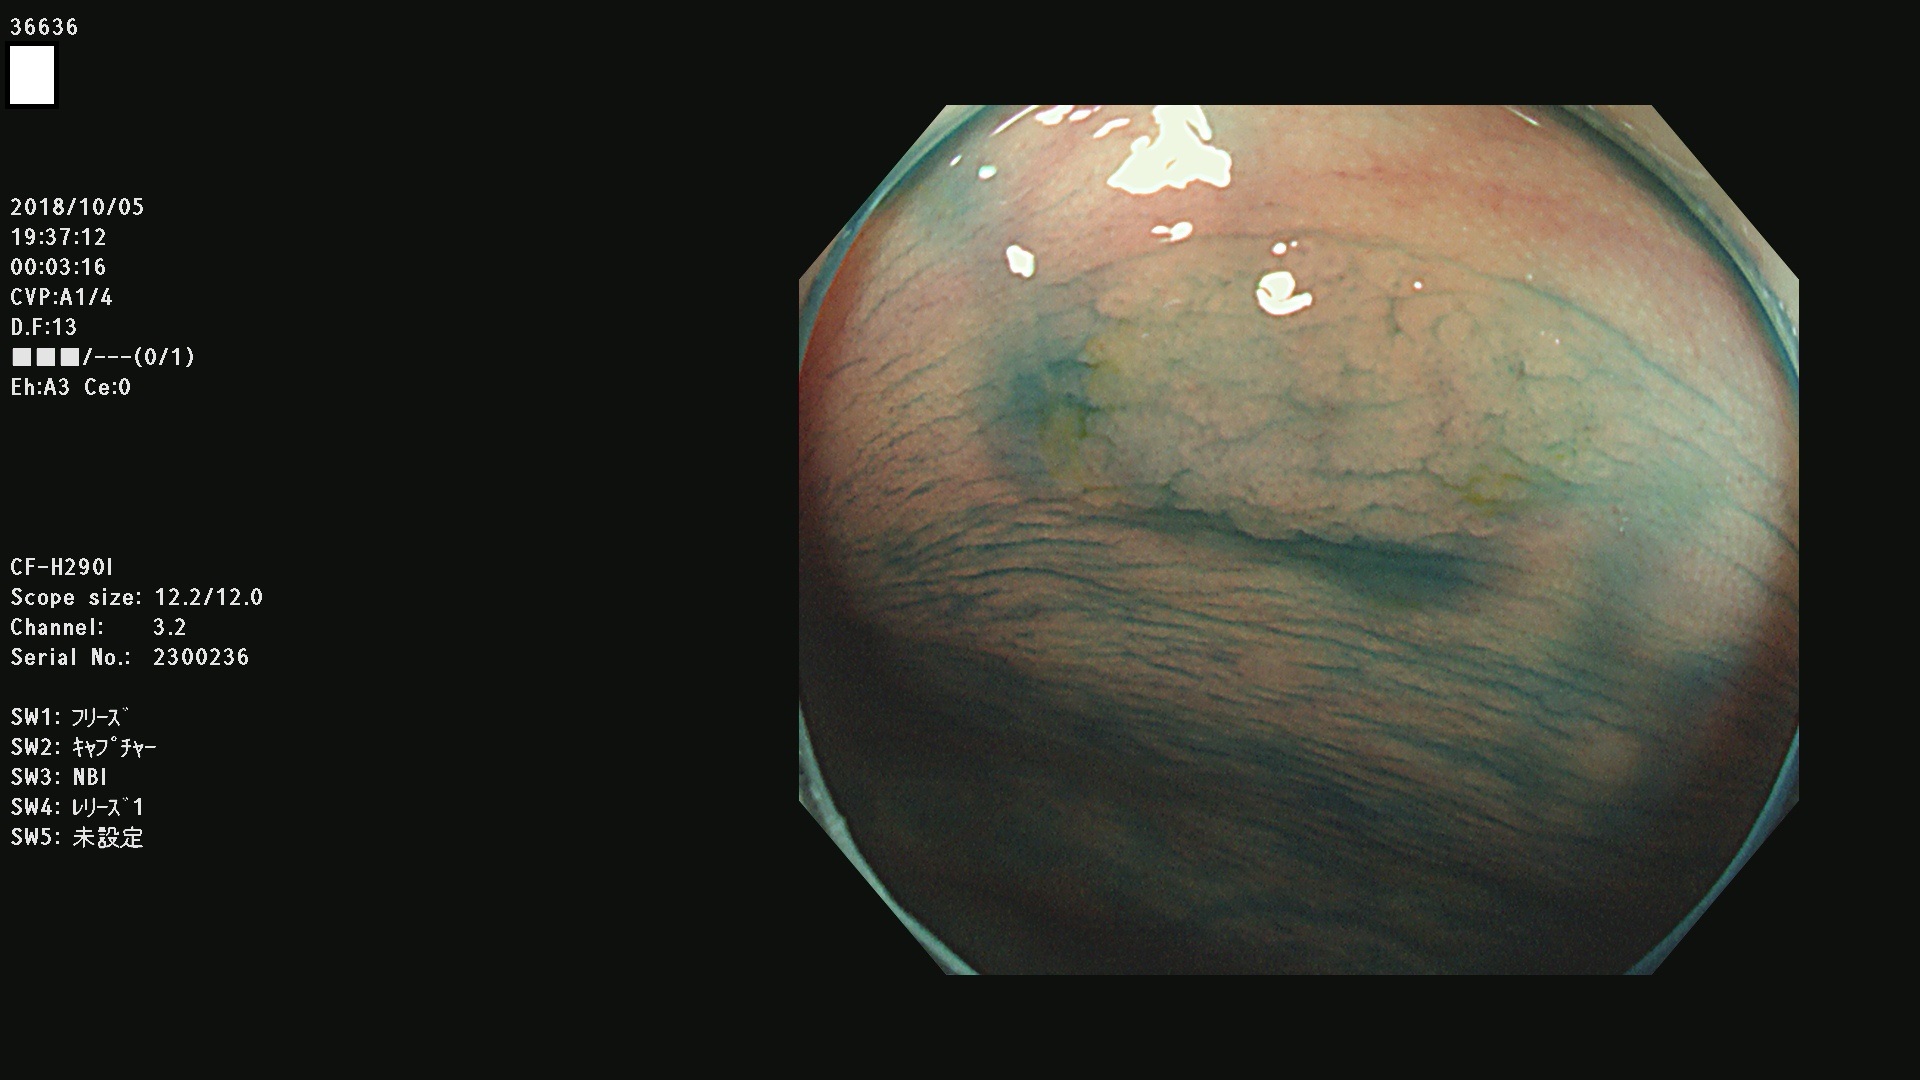

36600 36601 36603 36605 36606 36608 36609 36610 36611 36612 36613 36615 36617 36620 36621 36624 36625 36626 36627 36628 36629 36631(SSAPのみ) 36632 36633 36634 36636(SSAPのみ) 36637(SSAPのみ) 36639 36640 36642 36643 36644 36646 36647 36648 36649(SSAPのみ) 36650(SSAPのみ) 36652 36653 36654 36655(SSAPのみ) 36656 36657 36658 36659 36660 36661(SSAPのみ) 36665 36668 36669 36672 36673 36676 36677 36678 36679 36681 36682 36683 36684 36685 36687(SSAPのみ) 36691 36692 36693 36694 36695 36696 36697 36699(SSAPのみ)

発見困難で危険性の高い平坦型病変(上記100名より抽出)